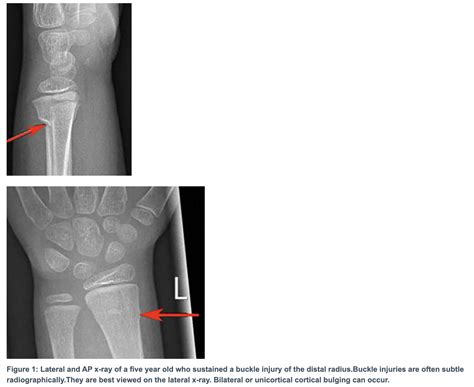

X-rays are the primary imaging tool used to diagnose a Buckle Fracture Radius. They provide a clear view of the bone and can show the characteristic buckling or compression of the bone.

• buckle fracture radius xray

• buckle fracture radius radiology